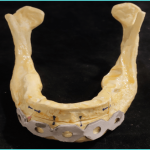

A 3D printed model of the mandible can also be printed to precontour the reconstruction plate12.

On the day of the surgery two surgical teams simultaneously resect the mandible and harvest the fibular graft using the previously printed stents, attach the reconstruction plate to the harvested fibular graft and then attach it to the remnant mandible; implants are placed there after using the stent. Following the implant placement there is a waiting period of 3-6 months for the graft to get accepted and implants to osseointegrate simultaneously.A prosthesis is then fabricated.